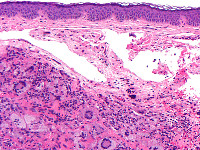

Infiltraat in de dermis bestaande uit histiocyten met een gevacuoliseerd, schuimig cytoplasma en ronde tot ovale kernen met een enkele nucleolus, en vaak met karakteristieke Touton-reuscellen. Daarnaast zijn er in wisselende mate reuscellen, lymfocyten en eosinofiele granulocyten aanwezig. Bij elektronenmicroscopisch onderzoek ontbreken de Birbeck-granula die typisch zijn voor de Langerhans-celhistiocytose. Bij vroege stadia kunnen de Touton-reuscellen en het schuimige aspect van het cytoplasma ontbreken. De cellen kleuren aan met de markers CD68, humaan macrofaag antigeen (HAM) 56 (een epitoop van CD68), factor XIIIa, cathepsine B, KiM1P (een pan-macrofaagmarker), KP1 (een epitoop van CD68) en vimentine, terwijl ze negatief zijn voor S100, CD1a en de macrofaagmarker Mac387.

Histologie juveniel xanthogranuloom Histologie xanthogranuloom

ingescande coupe (zoom) ingescande coupe (zoom)

Histologie xanthogranuloom Histologie xanthogranuloom

PA-Foto's boven: Michael Bonert (Nephron) - Wikimedia (Creative Commons License 3.0)

Hoge resolutie PA-foto's: Kevin Kwee en Afdeling Pathologie MUMC. Klik op de afbeelding om in te zoomen.